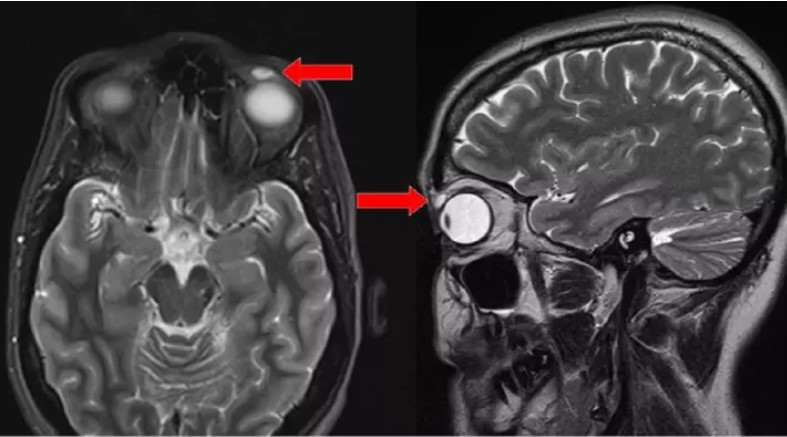

42 yaşındaki kadın, üst sol göz kapağında şişlik ile doktora gitti. Göz kapağında uzun bir süredir ağrı vardı ve şişmeye de başlamıştı. Dokunduğunda daha da çok ağrıyan bu şişlik için bir doktorlar önce kist dediler..

Ameliyatla müdahele için hazırlıklar yapılırken enfeksiyon kapıp şişen yerin aslında kırık bir lensi sakladığını görünce şaşkınlıklarını gizleyemediler. Bu lensler neredeye 28 yıldır piyasada sert lenslerdendi.. işin sırrı kadının anlattıkları ile ortaya çıktı.

Kadın genç bir kızken badminton maçında gözüne top çarpmış. Lensin düştüğünü varsayıp üzerine durmamış fakat lens kırılıp göz kapağından içeri girmiş. Tam 28 yıl sonra ise şişlikle tekrar ortaya çıkmış..